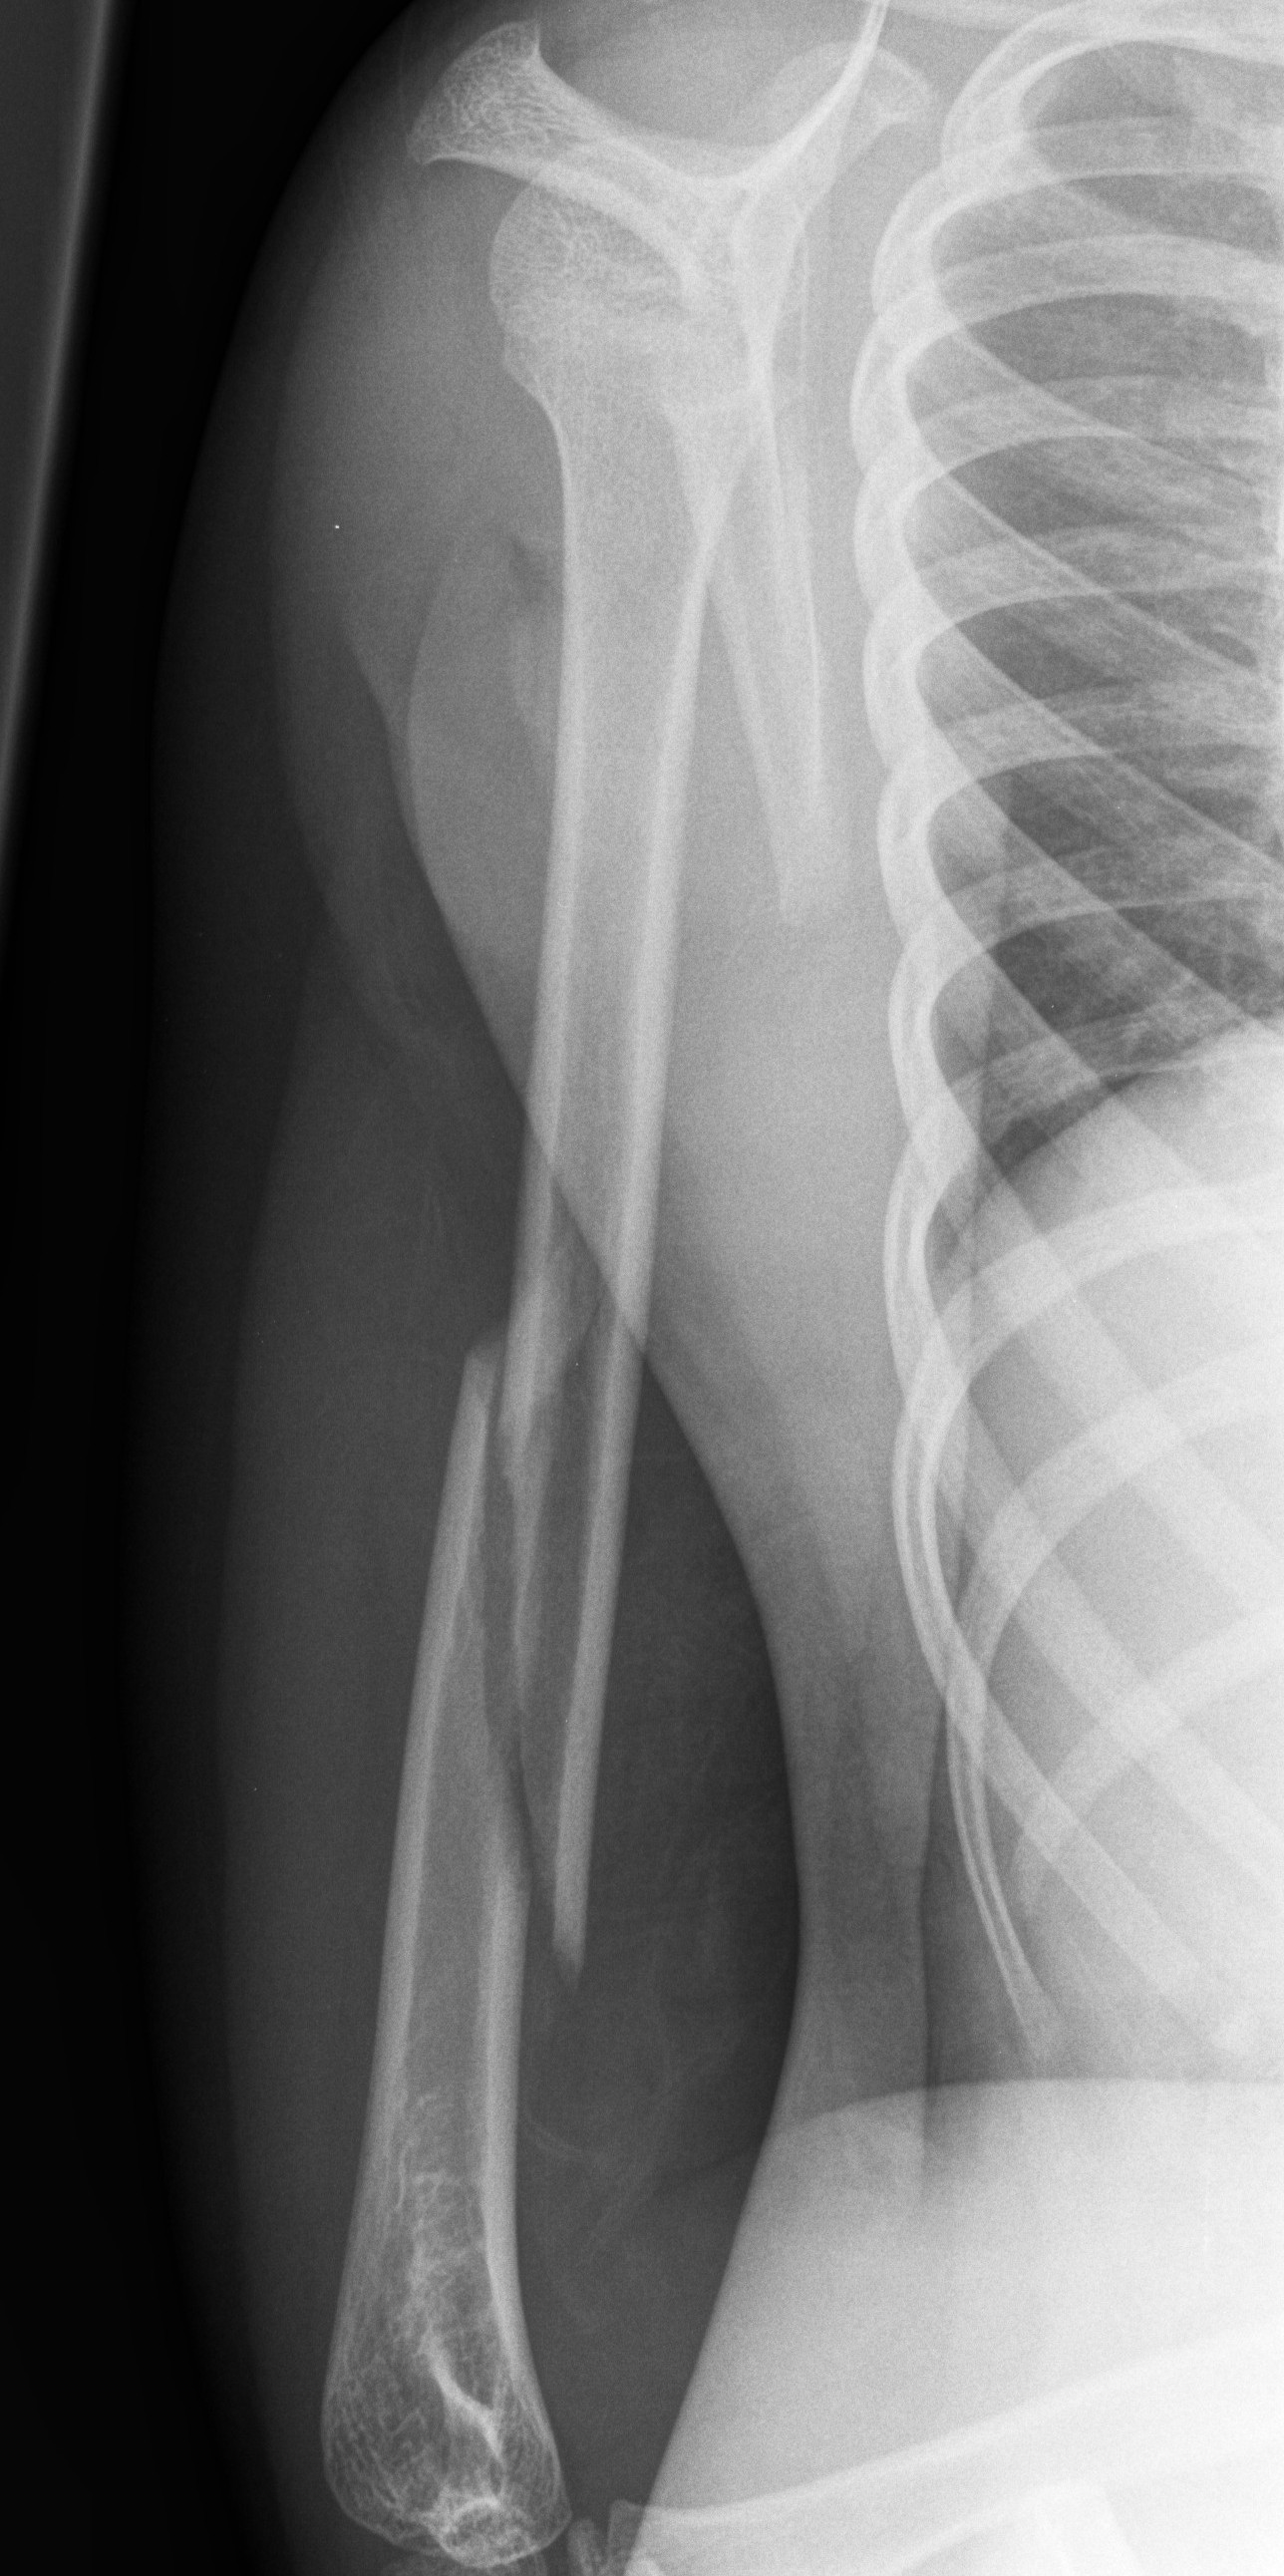

Spiral Fracture X-Ray . It occurs when a long bone is twisted with force. a spiral fracture is caused by supination of the foot with external rotation force (torsion injuries). The fracture line encircles the shaft like the stripes on a candy cane. spiral fractures are complete fractures of long bones that result from a rotational force applied to the bone. The fracture line encircles the shaft like the stripes on a candy cane. Spiral fractures may occur in. a spiral fracture is a type of bone fracture. A twisting force to the thigh causes this type of fracture. Radius and ulnar shaft fractures, also known as adult both bone forearm fractures, are common fractures of the forearm. This type of fracture is caused by a twisting force. It will appear similar to a corkscrew on an x.

Cureus Spiral Humeral Fracture During Arm Wrestling A Case Report Spiral Fracture X-Ray a spiral fracture is a type of bone fracture. It occurs when a long bone is twisted with force. The fracture line encircles the shaft like the stripes on a candy cane. A twisting force to the thigh causes this type of fracture. This type of fracture is caused by a twisting force. spiral fractures are complete fractures. Spiral Fracture X-Ray.